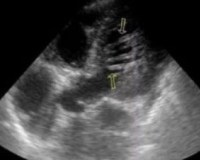

• Эхокардиография. На УЗИ сердца обнаруживается дополнительное линейное образование, не связанное с клапанным аппаратом. Для большей надежности пояс необходимо визуализировать в 2-х плоскостях, перпендикулярных друг другу. При ультразвуковом исследовании определяется толщина и длина спинного мозга, его подвижность в период сердечного цикла.